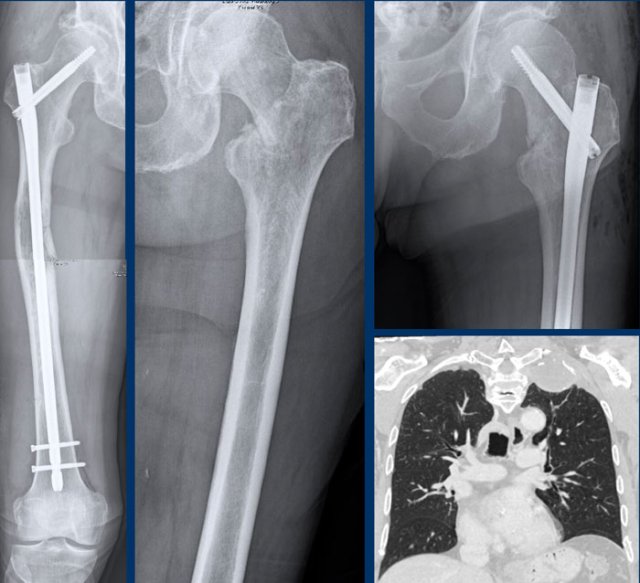

Dedifferentiated chondrosarcoma

First look at the images of a 79-year-old patient with a bone tumor.

Then continue reading.

Images

Radiographs show a large tumor in the femoral diaphysis with typical popcorn calcifications distally and a

more osteolytic component proximally.

Detailed magnified window of the

lateral view shows cortical permeation by the tumor and a high risk for a

pathological fracture.

The caudal part of the tumor appears

like an ACT with focal cortical scalloping, while the cranial part looks like a high grade CS.

Conclusion

This is the typical

presentation of a dedifferentiated chondrosarcoma, with one part behaving like a

low to intermediate grade cartilage tumor with abrupt transition to a

high-grade (sometimes non-cartilaginous) sarcomatous component.

This subtype

usually presents in older adults.

Overall survival of a dedifferentiated

chondrosarcoma is poor as compared to chondrosarcomas grade II and III, as

patients often present with pulmonary and bone metastases at the time of

diagnosis.

Continue with the next images...

Note the cortical defect on the axial

T2 DIXON and the surrounding soft tissue mass.

Part of the tumor does not enhance

and this area of mucoid indicates a high grade chondrosarcoma.

As on the radiographs, this

case is a typical dedifferentiated

chondrosarcoma, where the lower part behaves

like an ACT and the proximal part as a high grade sarcoma.

Frequently they present as a large tumor in an elderly patient.

Perfusion images demonstrate

heterogeneous enhancement within this dedifferentiated chondrosarcoma.

The mucoid part (blue line)

shows no enhancement.

Continue with the PET-CT...

We discussed before that 18F-FDG PET-CT is not recommended for chondrosarcoma to differentiate between ACT and high grade tumors.

However, in dedifferentiated

chondrosarcoma, PET CT combined with a diagnostic CT of the chest may be

performed to look for metastatic disease.

The dedifferentiated chondrosarcoma in

the right femur shows high FDG captation and the whole body image demonstrates multiple bone metastases in the left femur, left clavicle, cranial ribs on the

right and in the sternum.

Para-iliac lymph node metastases are

present bilaterally.

As chondrosarcomas are insensitive to radiotherapy and chemotherapy, the patient received palliative care, including nailing of the right femur to prevent a fracture.

Unfortunately, he developed a pathological fracture in the left femur which was subsequently treated.

Coronal CT image of the chest demonstrates the soft tissue mass around

a metastasis in the left clavicle.

No pulmonary metastases were found.

The prognosis of dedifferentiated chondrosarcoma is poor with a 5-year overall survival of about 18%.